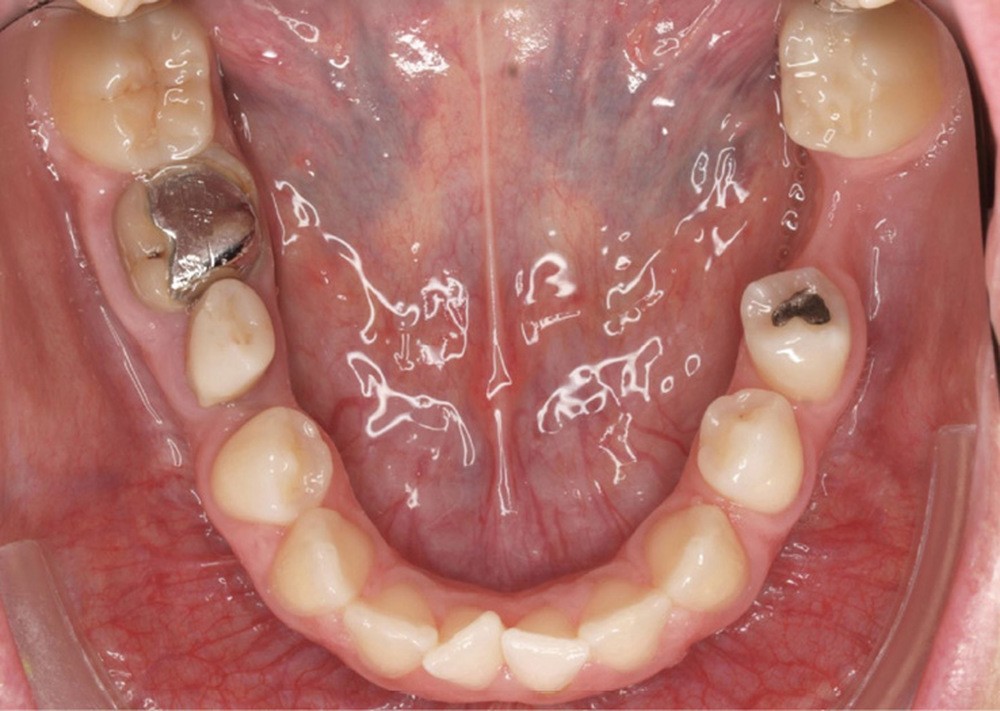

Diagnostic (fig. 1a-g)

La patiente présente une classe III squelettique dans un contexte hyperdivergent associée à une endoalvéolie maxillaire, un articulé inversé antérieur, une rétroversion incisive maxillaire, des rapports de classe I canine bilatérale, une absence de 16 et 36.

Au niveau esthétique, le profil est rectiligne. La lèvre supérieure est plus effacée, en retrait par rapport à la lèvre inférieure. De face et de profil, la mandibule paraît massive et le maxillaire effacé : le manque de soutien de la lèvre supérieure contribue à cette impression.

Le sourire est étroit, dégradé par les malpositions dentaires.

Au niveau fonctionnel, il existe un pro-glissement mandibulaire et un articulé inversé antérieur. Le profil téléradiographique montre en occlusion des rapports labiaux et un profil de classe III plus marqué que sur photographies.